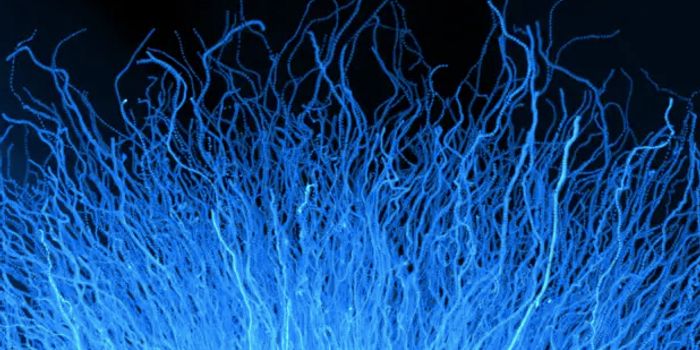

SEP 05, 2024Cell & Molecular BiologyCorynebacterium matruchotii ia a common bacterium that lives in human dental plaque; a colony is seen in this image by S ...